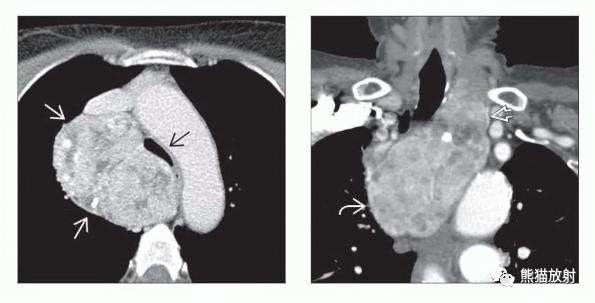

(左) 前纵隔甲状腺肿患者,轴位CECT显示前上纵隔较大肿块并气管受压,病变内包含一个小的乳头状癌。15%的甲状腺肿可发生隐匿性甲状腺恶性肿瘤。

(右) 起源于异位前纵隔甲状腺组织的纵隔甲状腺肿,CT平扫显示不均质肿块伴局部囊性成分和内在钙化。